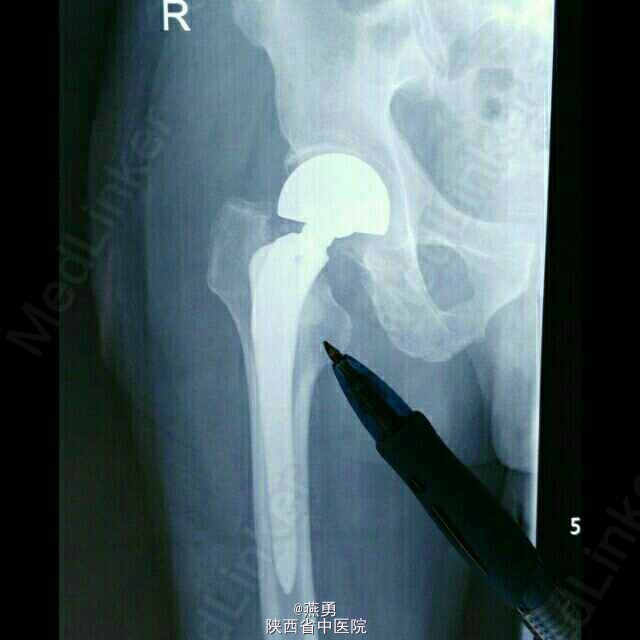

诊断:右股骨颈骨折,骨囊肿待查。治疗:右侧人工股骨头置换术,病灶清除探查术。麻醉生效后,常规逐层切开及暴露可见股骨颈颈中型骨折,清除周围纤维增生挛缩及瘢痕组织,取头器取出断裂的股骨头,患肢内收外旋脱位后,截骨,髓腔开口及扩髓,探针可见小转子内测约0.5*0.8cm病灶空腔,内壁完整,刮除腔内病灶送病检,填入少量抗生素型骨水泥,装入生物型股骨柄,置入双动头股骨头假体,复位,见右侧髋关节屈伸旋转活动良好,未出现脱位,双下肢等长。冲洗,清点纱布器械后,放置引流,关闭伤口加压包扎。 术后安返病房行预防感染预防血栓及对症治疗。